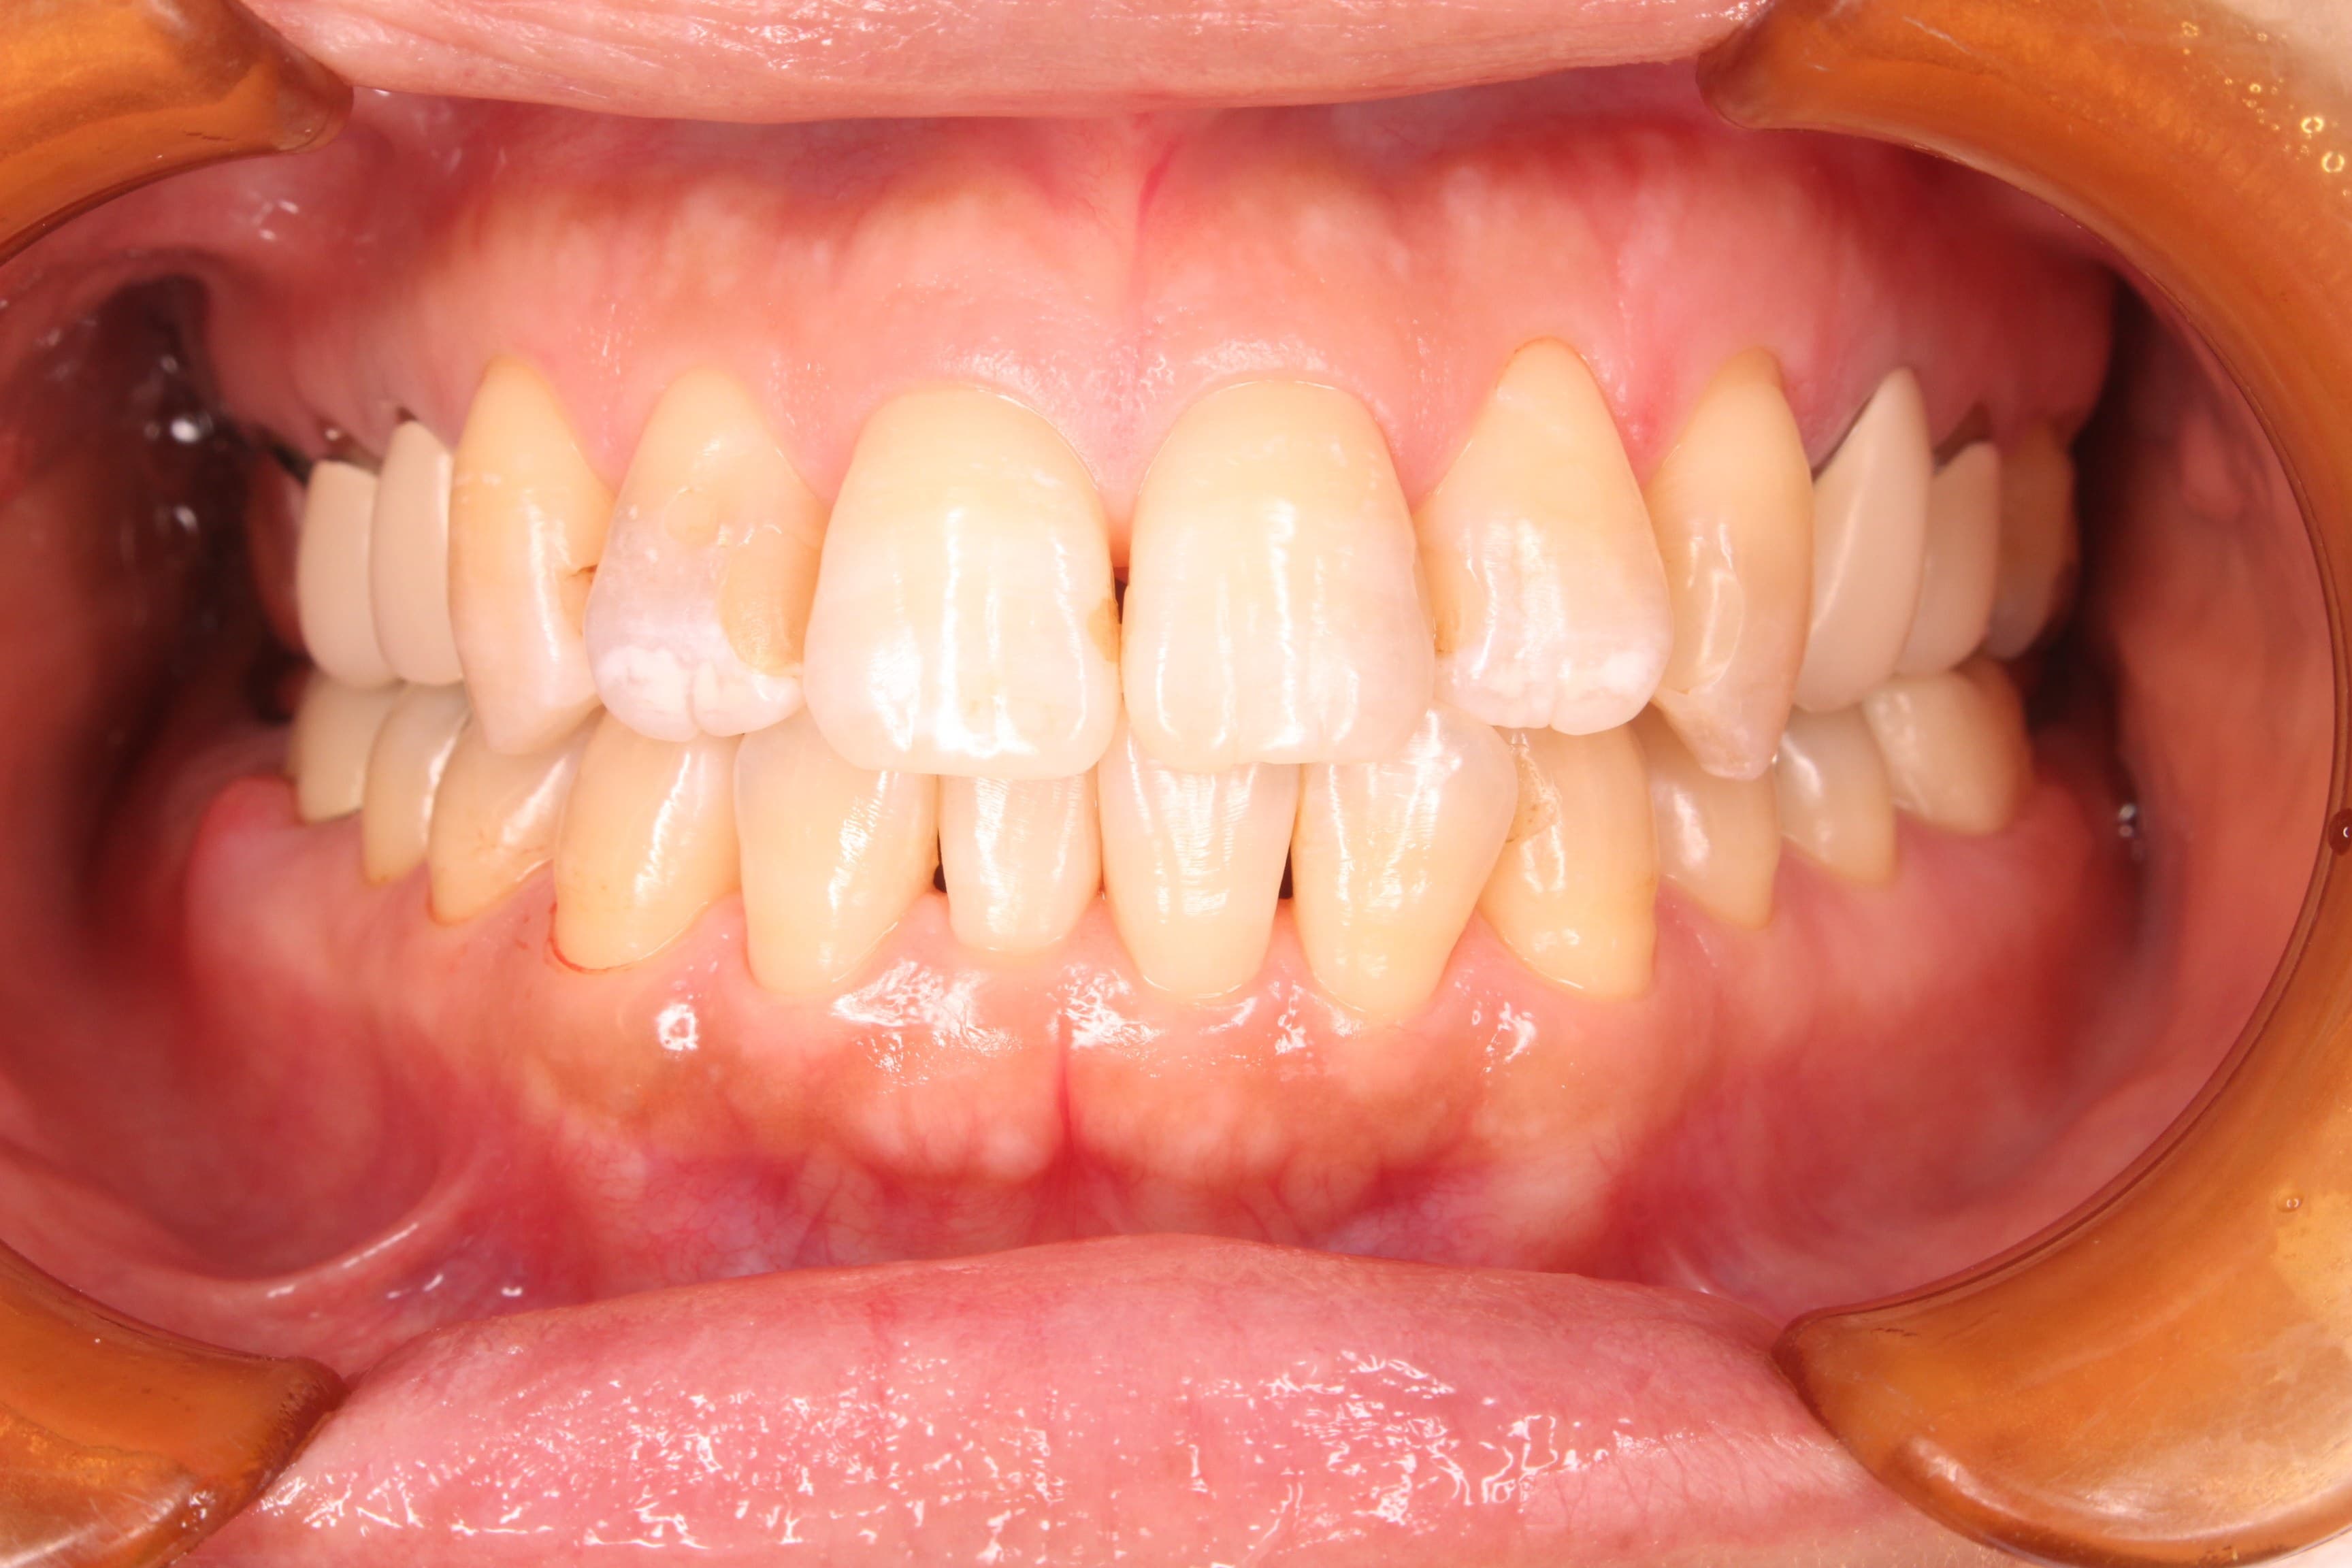

(治療後)

治療後、歯肉の状態もすごく良くなられて、今まで以上に家族の健康にも気を付ける様になったとのことでした。

病気が良くなったこともそうですが、何より〇〇さんの笑顔が増えた事が私はとてもうれしかったです。